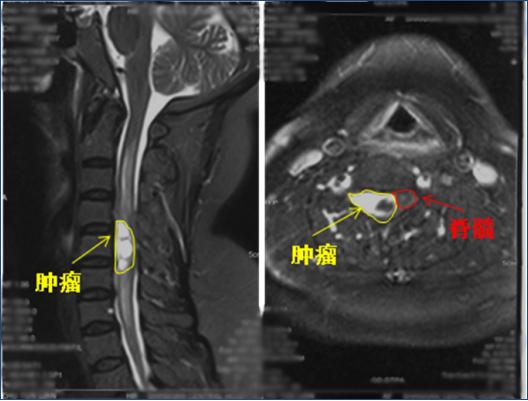

61岁的朱女士来自山东单县,入院半年前突然出现右侧颈肩部疼痛麻木,在当地医院反复就诊,先后诊断为“肩周炎、颈椎病”,曾尝试多种保守治疗方法,症状依然进行性加重。入院前一个月患者出现右上肢疼痛麻木,肌肉力量下降,吃饭、穿衣、睡觉等日常生活均受到严重影响,经颈椎磁共振检查发现其颈4—6水平椎管内有一个巨大肿瘤。

剥离过程轻巧准确,只见,位于颈4-6脊髓右腹侧的肿瘤被神经缠绕着,颈5右侧神经根部分神经束穿行于肿瘤内,同时肿瘤对颈5神经根也造成了严重压迫。程钢戈主任在显微镜下,一点点剥离显露肿瘤,一丝丝清除薄如蝉翼的脊髓粘连,直到将这一30×15×15毫米大小的肿瘤完整切除(如下图),丝毫未伤及任何神经组织。